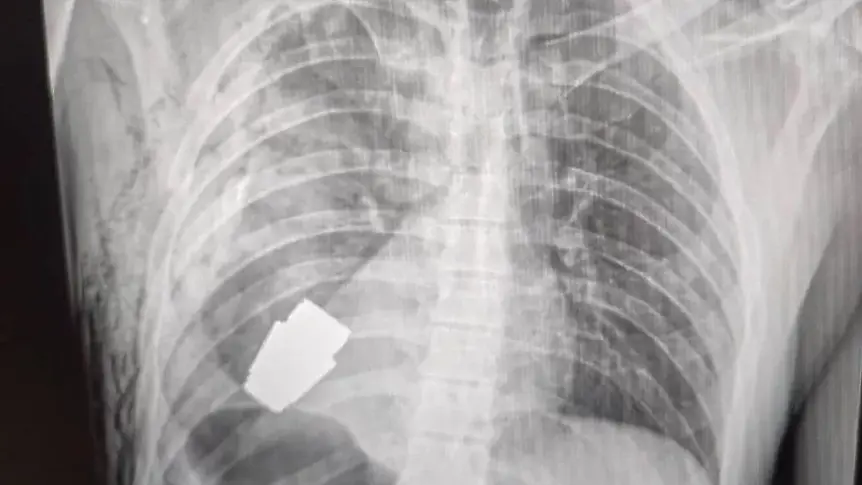

Снимки преди и след на фейсбук страницата на здравната работа на въоръжените сили на Украйна,показват рентгенова фотография на експлозив,близо до сърцето на военнослужещия и друга на хирурга, който държи окървавеното устройство.

Добавя се, че устройството е граната VOG - 4 см дълъг арсенал, който се изстрелва от гранатомет и може да измине към 400 м и е планиран да експлодира тъкмо над земята.